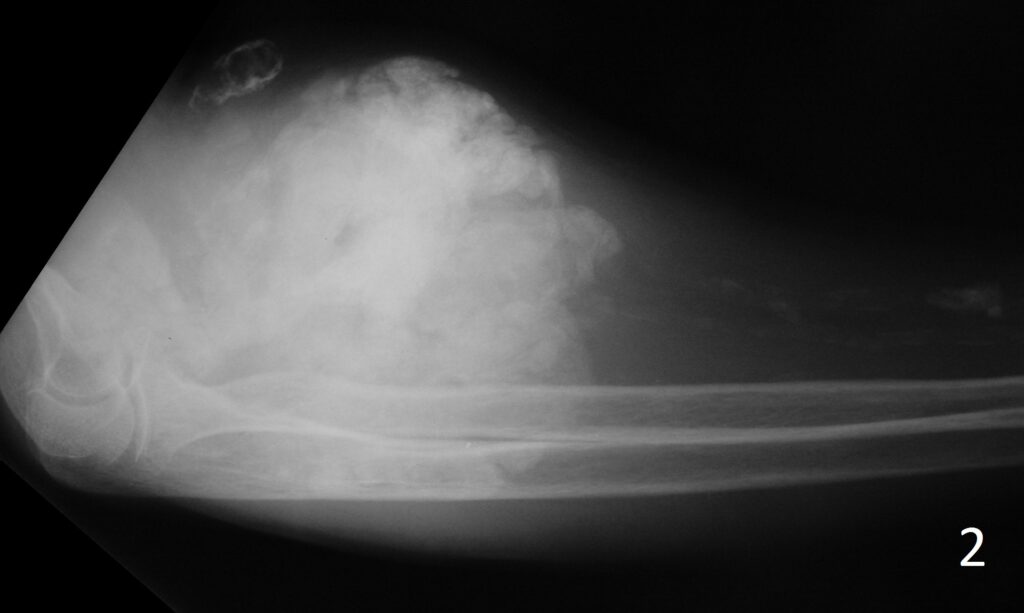

Plain x-ray (Fig. 1-2)

- Reveal well defined opacities in soft tissue

- Foci of calcification are few millimeters to 2 cm of size

- Lobulated calcifications separated from the bone

Fig. 1-2: AP (Fig. 1)and lateral (Fig. 2) xray of elbow show exuberant ossification around the elbow joint consistent with tumoral calcinosis in this patient with chronic renal failure.